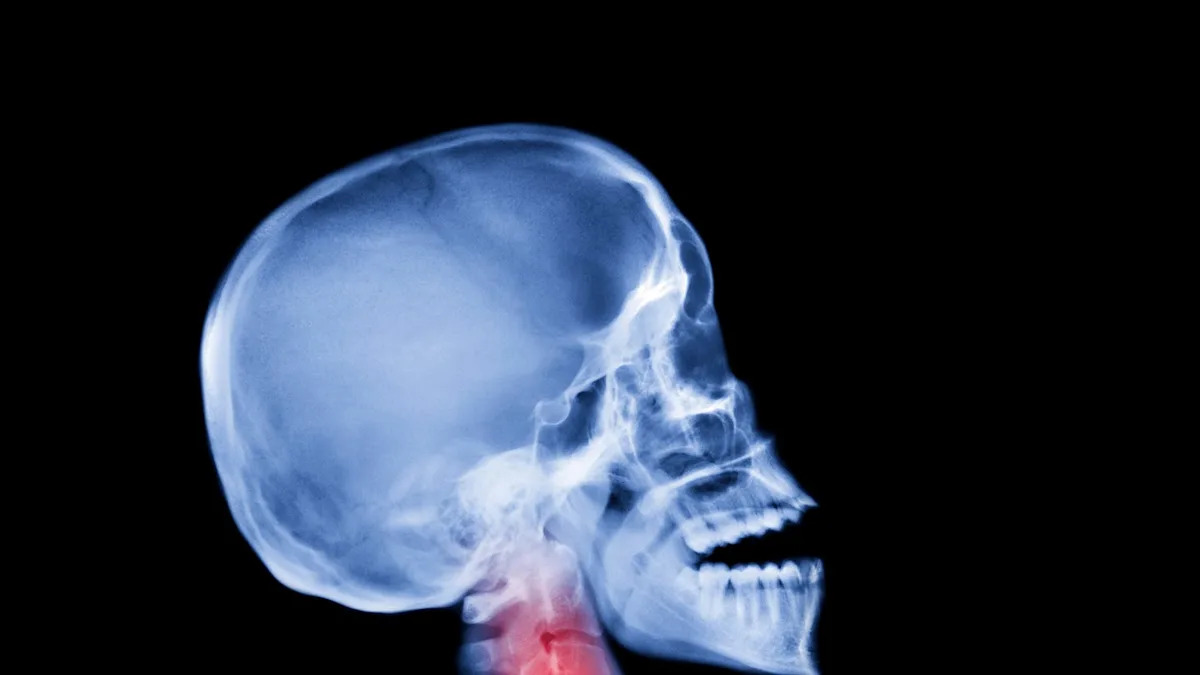

DNA study leads researchers to pin humanity’s low pain thresholds on Neanderthals.

Researchers in Europe say they’ve linked the genetics of ancient Neanderthal interbreeding to low thresholds for specific types of pain in modern humans. They published the findings in Communications Biology.

In the recent study on pain, researchers investigated three variations in the SCN9A gene, and reported greater pain sensitivity among humans carrying all three variants. The SCN9A gene builds sodium channels that help nerve cells communicate—in particular, it helps the cells alert the nervous system to a painful threat from damaged tissue.